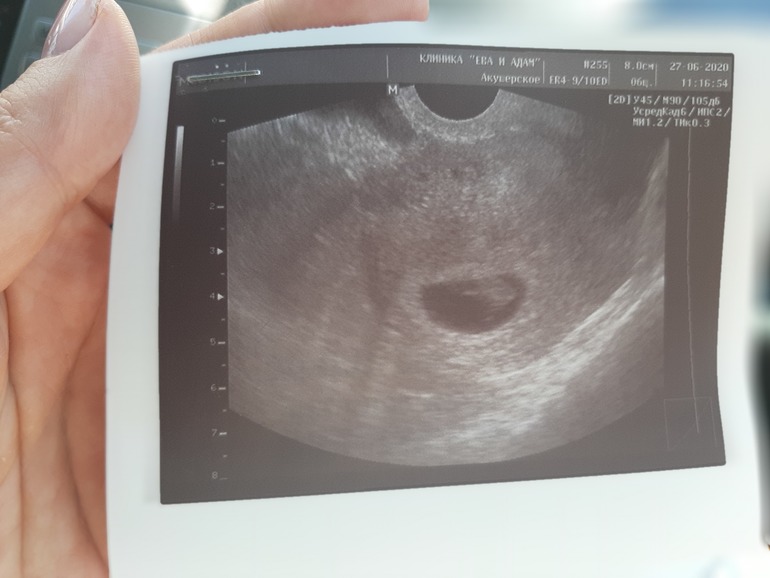

По последним месячным 7.3. По УЗИ 6.6 неделек. Говорит поздняя овуляция. Ну у меня цикл 32 дня так что на 20 день это не поздняя а обычная. Все хорошо. Есть там козявочка и сердечко стучит. Так радостно. Теперь можно строить планы и думать о своих симптомах. Запишу себе на память и другим для сравнения.